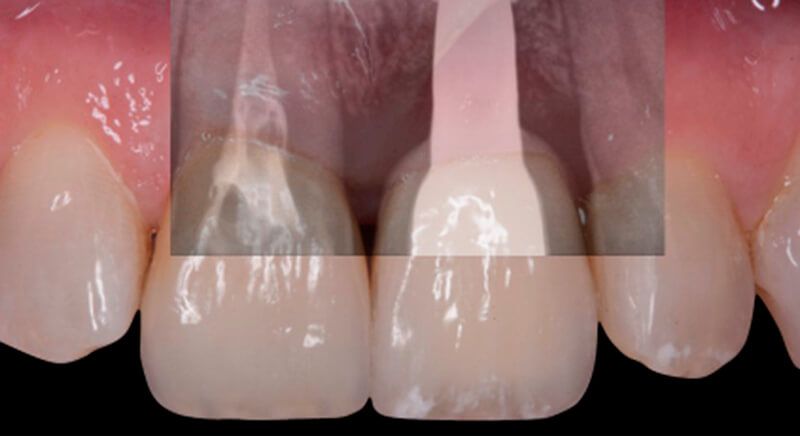

Finally, a definitive metal ceramic crown was designed and manufactured for 2.1 and a veneer for 1.1.